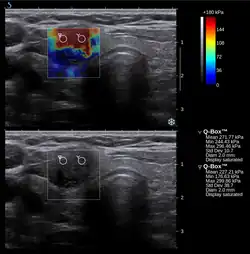

L'élastographie, créée par le Dr Jonathan Ophir en 1991[1], est une technique d’imagerie médicale pour mesurer l'élasticité du tissu biologique dans un organe.